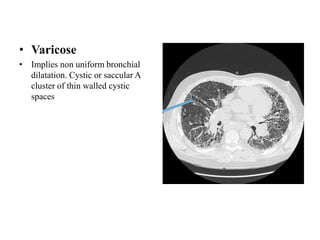

• Varicose

• Implies non uniform bronchial

dilatation. Cystic or saccular A

cluster of thin walled cystic

spaces